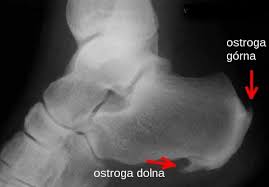

Ostroga piętowa jest nieprzyjemną dolegliwością obniżającą jakość życia. Ból może pojawiać się dosłownie przy każdym kroku, a w skrajnych przypadkach nawet w nocy, wybudzając ze snu. Często obrzęk spowodowany stanem zapalnym utrudnia wręcz włożenie buta na stopę. Po jakimś czasie w okolicy guza piętowego gromadzą się złogi wapienne, które łącząc się ze sobą, tworzą wyrośl kostną. Ostroga piętowa jest prostym schorzeniem do zdiagnozowania – przeważnie wystarczy do tego badanie wykonane przez lekarza ortopedę i zdjęcie rentgenowskie lub usg stopy dla potwierdzenia tezy specjalisty.

Body Move podaje, że zwykle wystarcza badanie ortopedyczne oraz zdjęcie RTG, a pomocniczo/confirmacyjnie może być wykonane także USG stopy.